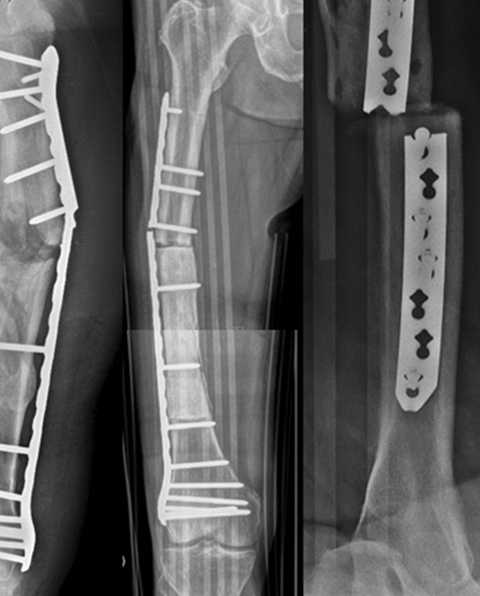

An X-ray showing a fractured plate, broken screw, bent intramedullary nail or failed fixation — the implant has fatigued before the bone healed. Implant failure confirms that the fracture has not united and the mechanical environment was inadequate. Broken hardware must be removed and the fracture re-fixed with appropriate revision fixation and — in most cases — bone grafting.

Broken Implant Removal & Re-fixation

Broken plate, fractured nail or failed screws — removed with specialised extraction equipment (broken screw extractors, trephines, reverse-cutting taps). Re-fixation with appropriate revision implant — exchange nail, longer locking plate or combined plate-and-nail construct. Bone graft added to address the biological deficiency that caused the implant to fatigue before the bone healed. CT scan pre-operatively to assess fracture gap, callus pattern and bone quality at revision.

Implant Failure